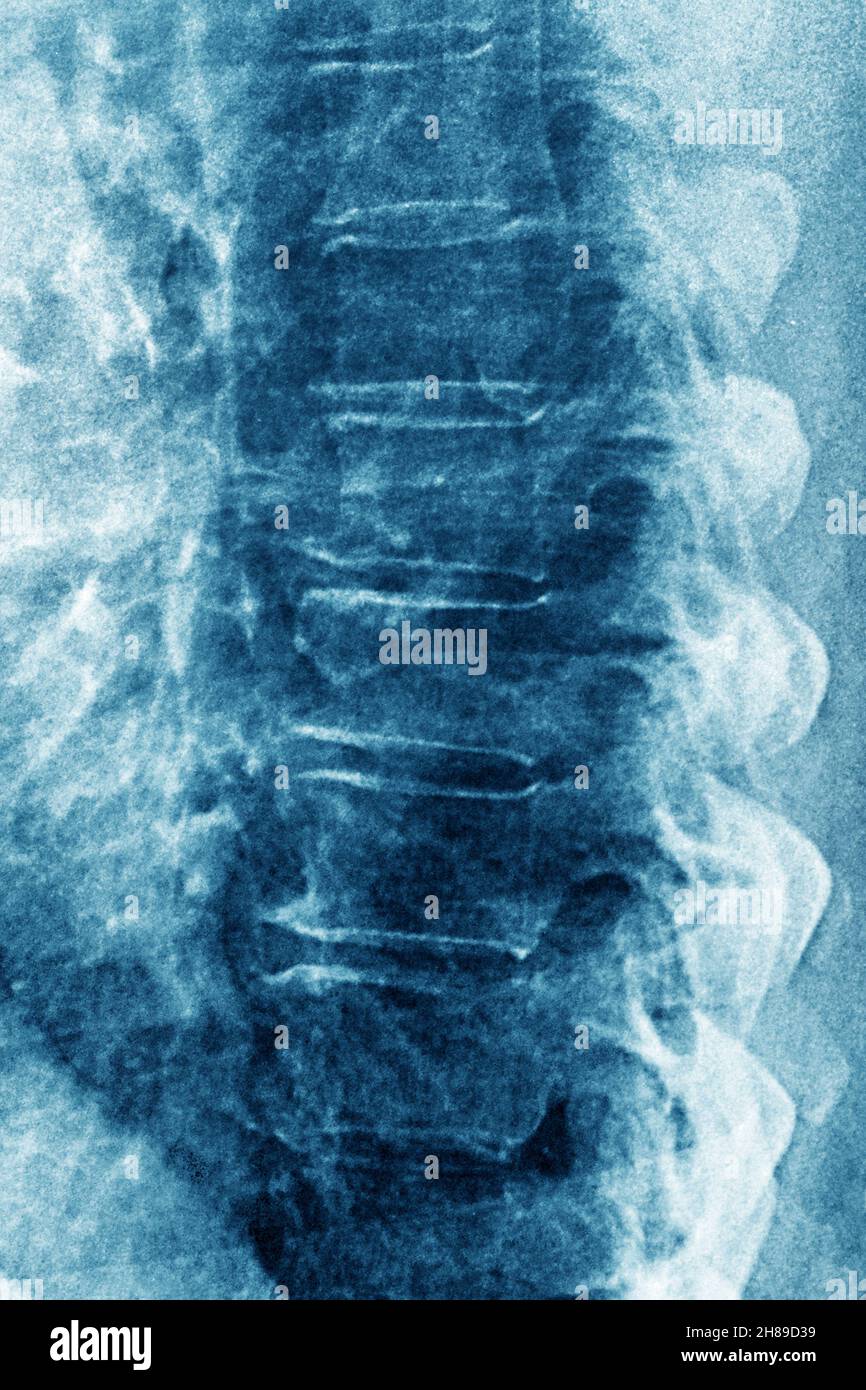

Lumbar Disc Disease Examples . outline the components of proper evaluation and assessment of a patient presenting with lumbar degenerative disc disease, including any. lumbar degenerative disk disease. Your lower back, or lumbar spine, has five vertebrae, which are the largest. the region in your neck area is the cervical spine, the region in your chest is the thoracic spine and the region in your low back is the lumbar spine. a herniated disk, which can occur in any part of the spine, most often occurs in the lower back. lumbar disk disease may occur when a disk in the low back area of the spine bulges or herniates from between the bony area of the spine.

Lumbar Disc Disease Examples lumbar disk disease may occur when a disk in the low back area of the spine bulges or herniates from between the bony area of the spine. Your lower back, or lumbar spine, has five vertebrae, which are the largest. outline the components of proper evaluation and assessment of a patient presenting with lumbar degenerative disc disease, including any. a herniated disk, which can occur in any part of the spine, most often occurs in the lower back. lumbar degenerative disk disease. the region in your neck area is the cervical spine, the region in your chest is the thoracic spine and the region in your low back is the lumbar spine. lumbar disk disease may occur when a disk in the low back area of the spine bulges or herniates from between the bony area of the spine.